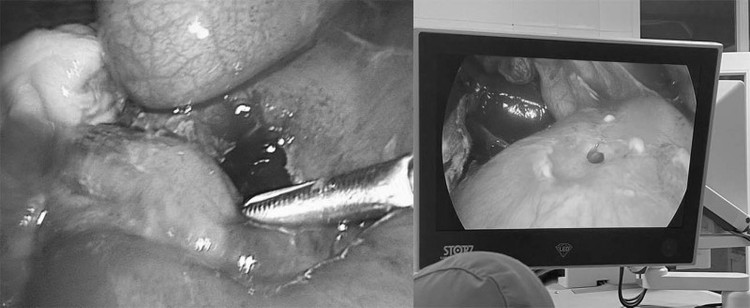

![]() |

| Phẫu thuật nội soi điều trị thủng tạng rỗng tại Bệnh viện Bãi Cháy. Ảnh BVCC |

Quá trình phẫu thuật nội soi, người bệnh được khâu lỗ thủng mặt trước hành tá tràng, lau rửa sạch dịch bẩn bằng 5l nước muối đẳng trương, dẫn lưu ổ bụng.

Các bác sĩ đã hội chẩn chuyên khoa chẩn đoán viêm phúc mạc do thủng tạng rỗng trên nền bệnh nhân có tiền sử phẫu thuật thủng dạ dày, tiến hành phẫu thuật nội soi cấp cứu khâu lỗ thủng hang môn vị, lau rửa sạch dịch bẩn, dẫn lưu ổ bụng. Hiện tại, sức khỏe của các bệnh nhân ổn định sau phẫu thuật.